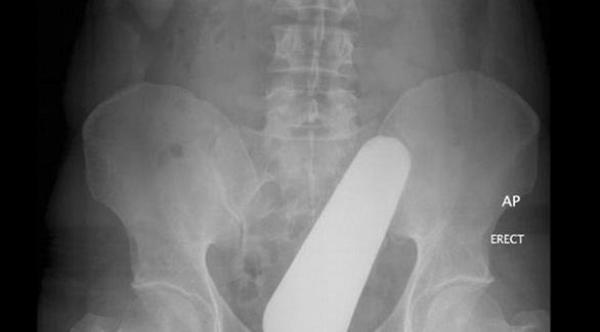

صورة لأشعة "إكس راي" توضح دخول أنبوب لعلبة فيتامينات.

صورة لأشعة "إكس راي" تُبين دخول باذنجان.

صورة لأشعة "إكس راي" توضح ابتلاع برتقالة كاملة بقشرها.